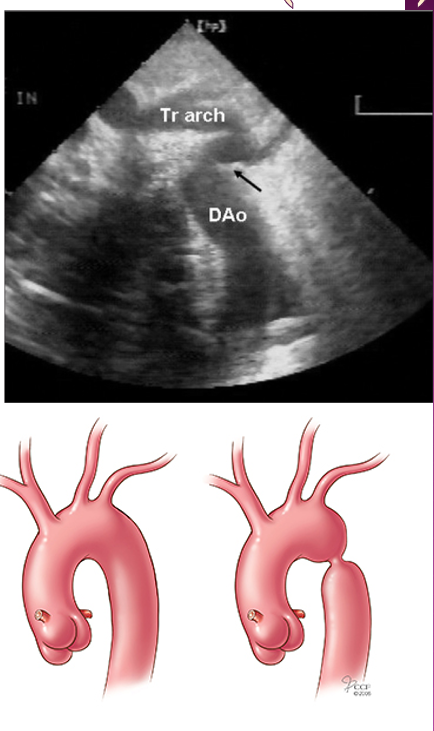

what is coarctation of the ao?

discrete narrowing or obstruction of the ao arch located in the descending ao

usually in area of ao isthmus

what is a juxtaductal coarctation?

narrowing of ao isthmus as its junction with prox descending ao at insertion of arterial duct (lig arteriosum)

basically where lig art inserts into ao

what are the types of coarctation?

A : ductal (juxtaductal)

B : preductal

C : post ductal

what is tubular hypoplasia and what does it typically affect?

tubular narrowing of entire ao arch segment

typically affects ao isthmus